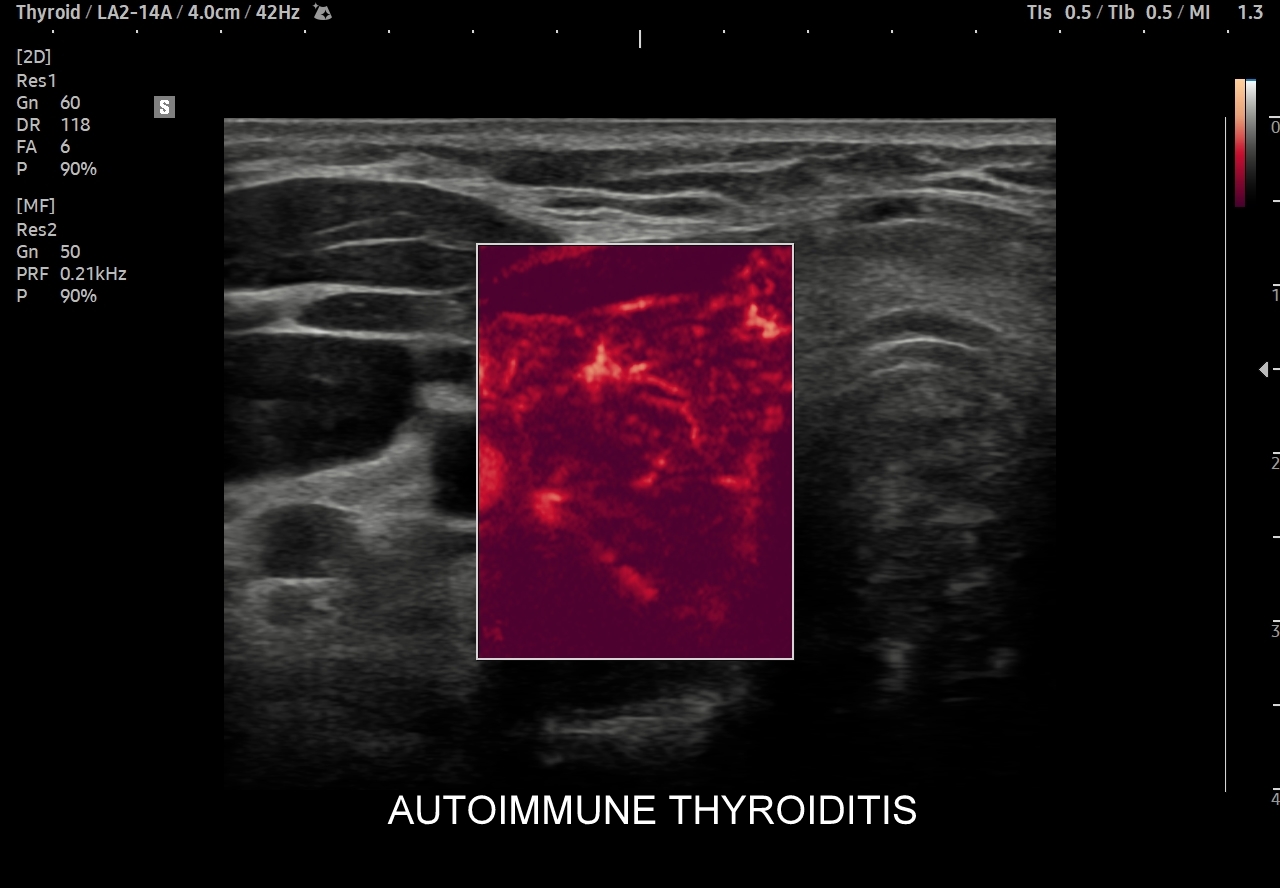

Multiparametryczne badanie USG (MPUS) jest rozwinięciem klasycznego USG tarczycy i szyi pod postacią jednoczasowego zastosowania różnorodnych technologicznie trybów obrazowania USG, zarówno tzw. „nowych”, jak i „starych”. Wśród nowych najważniejszym jest obrazowanie mikrounaczynienia (MVI / MVF), w dalszej kolejności tryb elastograficzny oraz B-flow. Wymienione „nowe” modalności w połączeniu ze „starymi”, przede wszystkim z Dopplerem spektralnym i color-Dopplerem, stanowią rdzeń nowoczesnej ultrasonografii MPUS, gdyż umożliwiają pozyskanie znacznie większej ilości informacji z badania USG szyi w porównywalnym przedziale czasowym, a przez to uzyskanie jego większej wartości diagnostycznej.

Przykładowo badanie MPUS umożliwia różnicowanie guzów, ocenę żywotności tkanek i biologii nowotworów, poprawia obrazowanie dużych naczyń krwionośnych oraz ocenę podejrzanych torbieli. Z kolei zastosowanie badania USG z kontrastem (CEUS), jako kolejnej modalności rozszerzającej MPUS, daje w wyselekcjonowanych przypadkach korzyści m. in. w postaci różnicowania i oceny zmian ogniskowych, czy oceny skuteczności terapii ablacyjnych.